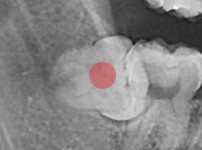

부분 매복 사랑니 발치

조회

797

작성일

26-01-02